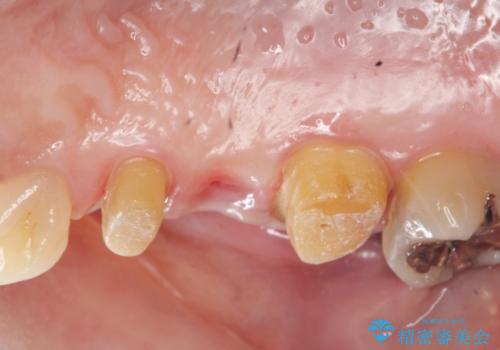

- 大きく歯が欠けてしまった虫歯の治療を希望され来院されました。

虫歯による歯の崩壊で歯を残すことが難しかったので抜歯を行い、インプラント・入れ歯ではなくブリッジによる咬合機能の回復を希望されました。